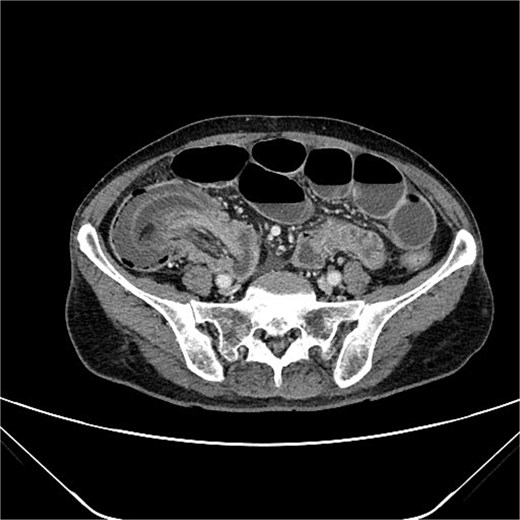

Imaging plays a central role in the diagnosis of intussusception. Abdominal computed tomography (CT) with contrast is considered the gold standard due to its high sensitivity and specificity. In adult cases, CT typically shows the characteristic “target” or “sausage-shaped” mass, which reflects the telescoping of one bowel segment into another [4].

A 76-year-old female patient presented to the emergency department with abdominal pain and vomiting. A standard radiography (Fig. 1) and a contrast-enhanced abdominal CT scan revealed an intestinal obstruction caused by intussusception of the terminal ileum into the cecum (Figs 2 and 3). Laboratory tests showed elevated C-reactive protein levels and leukocytosis. Her medical history was significant for bilateral carotid artery stenosis (under treatment with clopidogrel), mild obstructive sleep apnea syndrome, and hypertension.

The patient exhibited classical symptoms of bowel obstruction (abdominal pain and vomiting), confirmed by imaging studies. The elevation of inflammatory markers suggested a more advanced disease stage, possibly with localized inflammation or ischemia. The patient’s prior medical history did not directly influence the intussusception, but these comorbidities required careful perioperative management. The CT scan clearly demonstrated intussusception of the terminal ileum into the cecum, which is consistent with an ileocolic intussusception, a relatively common form in adults. Given the clinical and radiological findings, the patient underwent urgent laparoscopic right hemicolectomy with extracorporeal anastomosis.

Intussusception is described as the telescoping of one bowel segment with its mesenteric fold into an adjoining bowel tract, causing venous congestion and blood supply reduction. Intussusception can occur anywhere along the small and large bowel. This condition in adults poses diagnostic and therapeutic challenges due to its rarity and the nonspecificity of symptoms. Most adult cases are associated with an underlying lesion, often neoplastic, benign [8] or malignant (metastatic lesions, lymphomas, and adenocarcinomas), which underscores the importance of surgical resection and histological analysis [5]. The use of contrast-enhanced CT has greatly improved the preoperative diagnosis of intussusception, allowing for early and accurate identification of the condition. CT scan shows a peculiar sign, described either as “target,” “bulls- eye,” or “sausage-shaped” lesion (Fig. 3). This pathognomonic sign can be identified at coronal and axial view [5]. This case emphasizes the need for a high index of suspicion in elderly patients presenting with bowel obstruction and nonspecific abdominal symptoms. Prompt surgical intervention, as performed in this case, is crucial to prevent complications such as bowel ischemia or perforation, which significantly increase morbidity and mortality. Moreover, in this case, an underlying potentially malignant evolving condition was discovered and removed. Given the patient’s overall clinical status and the urgency of the situation, the choice of surgical management was appropriate.